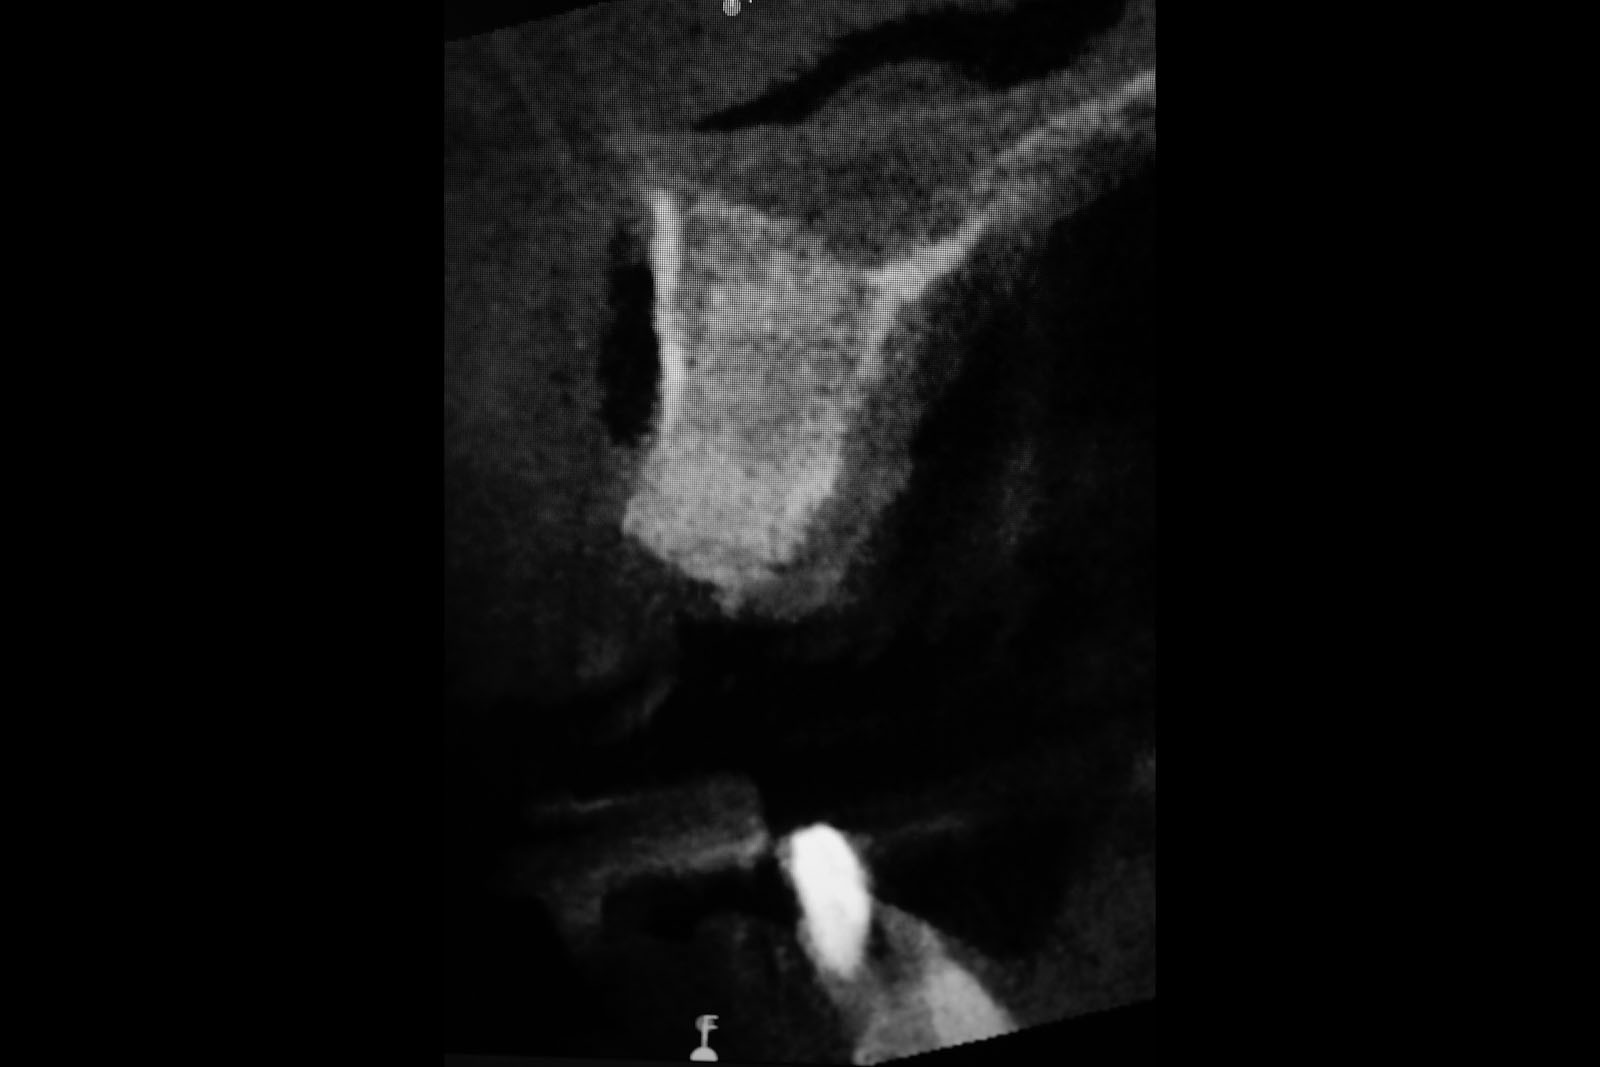

Przed podjęciem leczenia należy określić stopień zaniku kości szczęk oraz żuchwy. W tym celu przeprowadza się badanie kliniczne oraz odpowiednią diagnostykę obrazową pacjenta. Uwzględnia ona zdjęcie panoramiczne OPG jako podstawę dwuwymiarowego obrazowania podłoża kostnego oraz możliwe jest badanie tomograficzne CT lub bardziej precyzyjna tomografia stożkowa CBCT. Opcjonalnie wykorzystywana diagnostycznie tomografia pozwala na bardziej wnikliwą ocenę stopnia zaniku kości w trójwymiarowym, przestrzennym obrazie.

Zabiegiem, który rozwiązuje ten problem, jest podniesienie dna zatoki szczękowej, czyli odbudowa kostna w okolicy zębów trzonowych. Ubytek kości uzupełniany jest materiałem kościotwórczym, który układany jest pod błoną wyścielającą zatokę szczękową, zwaną membraną Schneidera. Zmniejszając objętość zatoki szczękowej, tworzy się tym samym stabilną strukturę kostną, umożliwiającą zabieg implantacji wszczepów śródkostnych.

Zatoki szczękowe to symetrycznie umieszczone w kościach szczęk przestrzenie powietrzne, posiadające komunikację z jamą nosa. Średnio pojemność zatok wynosi 24 cm3, a ściany wyścielone są błoną śluzową (membrana Schneidera). Dno zatoki szczękowej stanowi wyrostek zębodołowy, w którym umieszczone są zęby, często zlokalizowane tuż pod cienką wyściółką zatoki. Statystycznie najwęższy obszar kostny w tej strefie zlokalizowany jest na wysokości zębodołów pierwszego i drugiego zęba trzonowego.